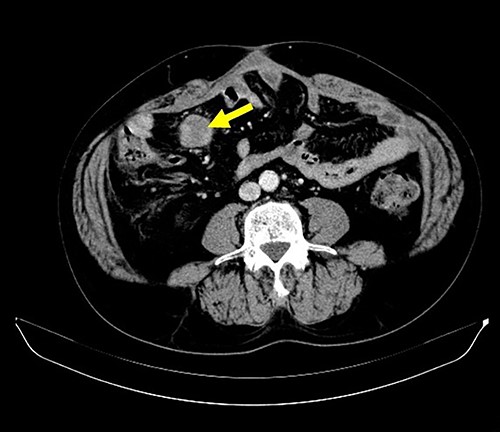

A 62-year-old man underwent distal gastrectomy for gastric cancer. The pathological diagnosis was pT3N0M0 Stage IIA according to the TNM Classification of Malignant Tumors, 8th Edition. In our hospital, follow-up chest and abdominal CT are performed every 6 months for 5 years after gastrectomy. About 2 years later, follow-up CT scan revealed a mesenteric tumor. CT also showed the absence of the other evidence of recurrence of the gastric cancer, such as ascites, distant metastatic tumor and remnant gastric tumor (Fig. 1). The mesenteric tumor had not been identifiable on previous images after gastrectomy; thus, this image was the first image on which GIST was identified. Positron emission tomography (PET)-CT was performed to evaluate the mesenteric tumor and identify other tumors, showing that the maximum standardized uptake value (SUV max) of the mesenteric tumor was 2.9, with no other tumors present in the entire body (Fig. 2). The mesenteric tumor was deemed to be a resectable tumor such as a GIST, desmoid tumor or malignant lymphoma, and not peritoneal dissemination because CT and PET-CT revealed no other tumors.

CT finding. Follow-up CT after gastrectomy for gastric cancer revealed a mesenteric tumor. There were no other malignant findings.